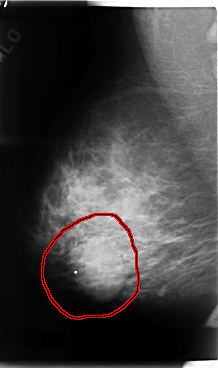

FILE: C_0076_1.RIGHT_CC.OVERLAY

TOTAL_ABNORMALITIES 1

ABNORMALITY 1

LESION_TYPE MASS SHAPE LOBULATED MARGINS MICROLOBULATED

ASSESSMENT 4

SUBTLETY 5

PATHOLOGY MALIGNANT

TOTAL_OUTLINES 1

BOUNDARY